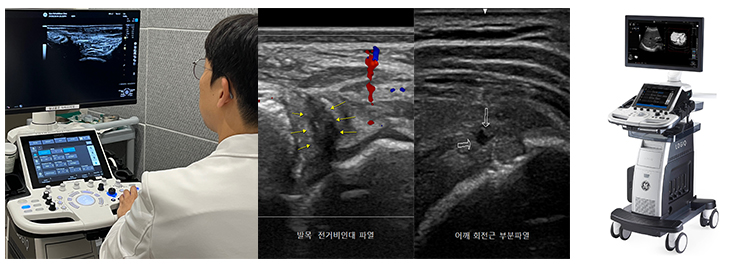

근골격계 초음파검사(Musculoskeletal Ultrasonography)

본원에서는 풍부한 임상 경험과 자격을 갖춘 전문의(대한초음파학회 검사인증의)가 초음파 검사를 시행하며, 이를 통해 회전근개 파열, 오십견, 테니스 엘보, 아킬레스건염, 발목 인대 파열, 족저근막염 등 다양한 병변을 정확하게 진단할 수 있습니다. 또한 초음파를 이용해 신경과 혈관 등 위험한 부위를 구분함으로써, 병변 부위에만 정확하게 주사를 놓을 수 있어 더욱 안전하고 효과적인 치료를 제공합니다.

검사 시간은 5~10분 정도로 매우 짧으며, 의료진과 환자가 함께 관절을 직접 움직여가며 인대나 근육의 이상이 있는 부위를 즉시 확인할 수 있습니다.